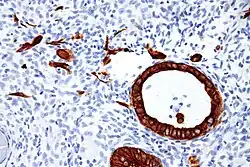

Histomorphology

- Implantation site intermediate trophoblast[1]

- pleomorphic irregular nuclei, large and hyperchromatic, may show multinucleation

- abundant eosinophilic to amphophilic cytoplasm

- infiltrative growth (splitting muscle, replacing vascular wall ...etc)